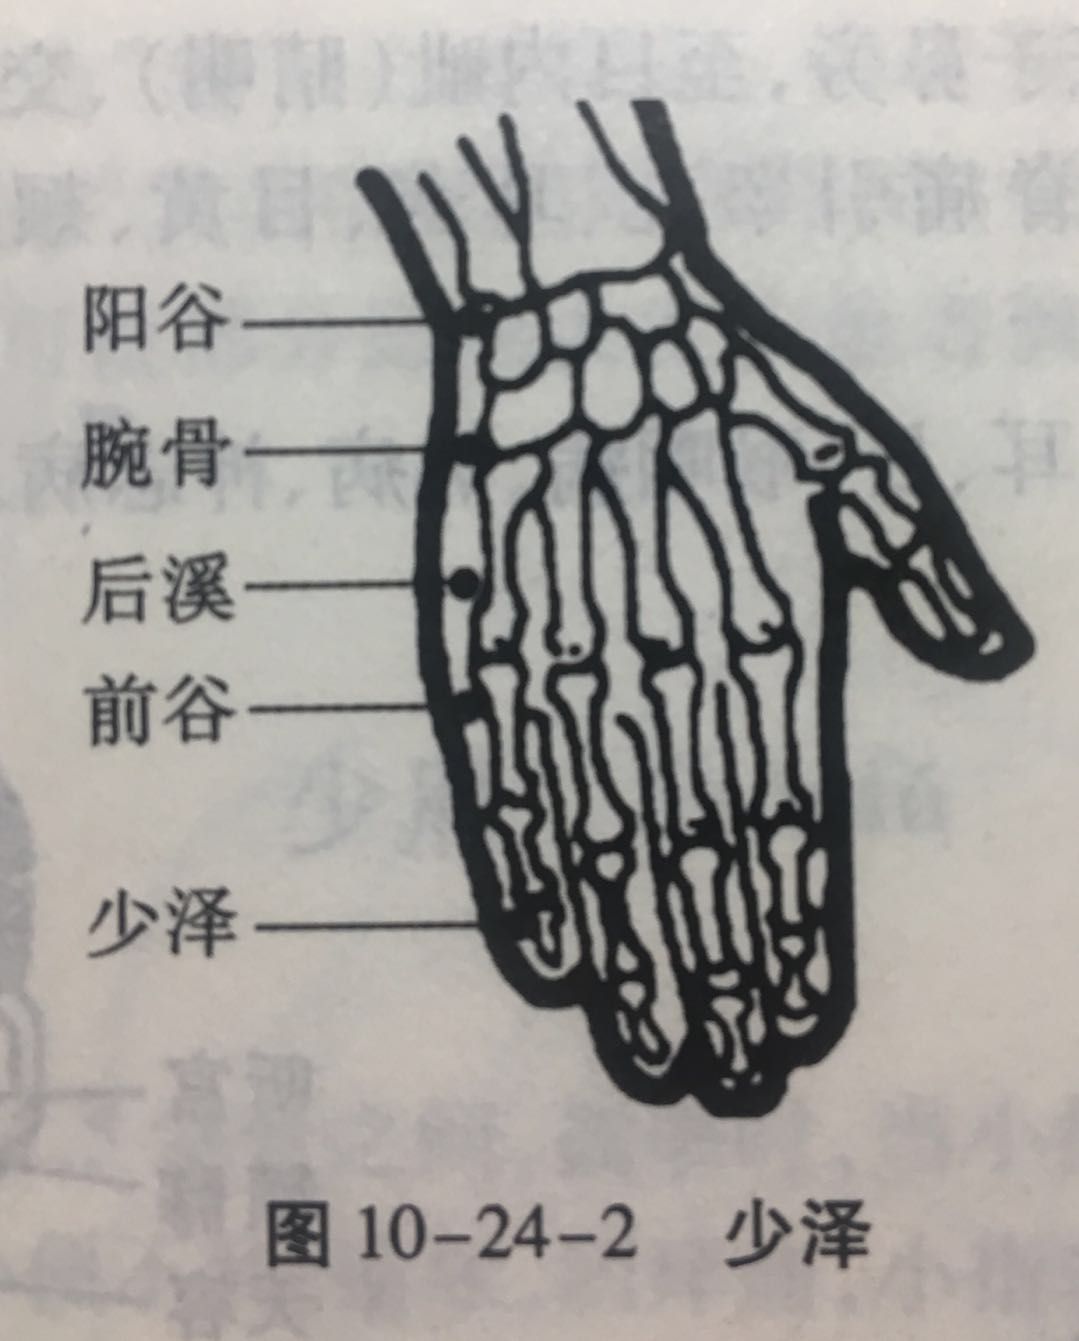

少泽

【定位】 在小指末节尺侧,距指甲角 0.1 寸(图 10-24-2)。

【主治】 头痛,目翳,咽喉肿痛,乳痈,乳汁少,昏迷,热病。

【配伍】 配膻中、乳根治乳汁少、乳痈。

【刺灸法】 浅刺 0.1 寸或点刺出血。

【附注】 手太阳经所出为“井”。

后溪

【定位】 在手掌尺侧,微握拳,当小指本节(第 5 指掌关节)后的远侧掌横纹头赤白肉际。